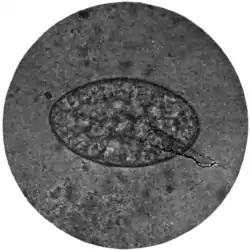

Fig. 168.—Ova of nematodes.

a, Strongylus subtillis; b, Ankylostomum duodenale; c, Trichiuris trichiura; d, Strongyloides starcoralis; e, Necator americanus; f, Ascaris lumbricoides; g, Ascaris lumbricoides (unfertilized).

Ova of Trichiuris trichiura (Fig. 168, c).—Of the three common nematodes mentioned—Trichiuris trichiura, Ascaris lumbricoides, and Ankylostomum duodenale—the ova of the first are the most frequently met with. They occur sometimes in enormous numbers, as many as six or eight specimens being visible in one field of an inch objective. They form a rather striking object under the microscope (Fig. 170). They are oval, measuring 51 to 54 μ by 21 to 23 μ, the ends of the long axis of the oval being slightly pointed and tipped with a little shining projection or plug. Their general appearance suggests an elongated oval tray, the projections at the poles of the ovum representing the handles of the tray. They are dark brown in colour, sharply defined, doubly outlined, and contain no differentiated embryo.

The ova of Ascaris lumbricoides (Fig. 168, f, g, and Fig. 171) are considerably larger (60 to 75 μ by 40 to 58 μ) than those of trichiuris (Fig. 168, c). They are also, as a rule, more spherical, or rather, more broadly oval; occasionally they are almost barrel-shaped. Like those of trichocephalus, they are dark brown in colour from bile-staining, but they are much less sharply and smoothly defined, possessing a coarse thick shell which is roughened by many warty excrescences. The yolk contents are not always easily made out, nor, when made out, can any sign of embryo or segmentation be discovered.

The ova of Ankylostomum duodenale (Fig. 168, b) contrast very markedly with both the foregoing, particularly in the matter of colour. Trichocephalus and ascaris ova are invariably dark and bile-stained; those of the ankylostomum are beautifully clear and transparent; they measure 55 μ to 65 μ by 32 μ to 43 μ; have a regular, somewhat elongated oval form, with a delicate, smooth, transparent shell, through which two, or four, or eight light-grey yolk segments can be distinctly seen. It is well to search for these ova soon after the fæces have been passed; otherwise, owing to the rapidity with which, in favourable circumstances, development proceeds, the embryo may have quitted the shell and the egg be no longer visible.